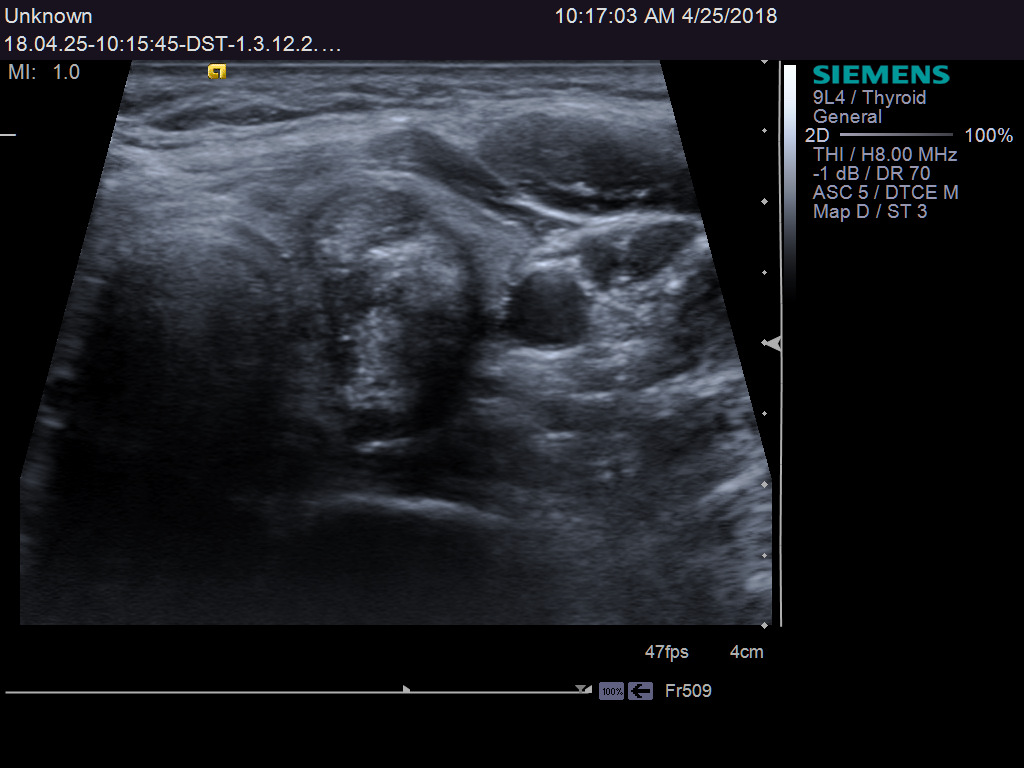

TI-RADS 4. Узлы более 1,0 см в диаметре с “малыми” признаками злокачественности для выполнения ПУНКЦИИ (рис. 3):

- солидные узлы, равномерно или неравномерно умеренно пониженной эхогенности;

- солидные узлы изо- или гиперэхогенные, имеющие “малые” признаки злокачественности:

– гипоэхогенные включения;

– округлая/шаровидная форма;

– неравномерно утолщенное хало;

– макрокальцинаты.

Рис. 3. TI-RADS 4: а – узел шаровидной формы, с ровными и четкими контурами, умеренно пониженной эхогенности, с участками более низкого эхо, с макрокальцинатом. Узел окружен тонким хало (фолликулярная неоплазия); б, в, г (поперечное и продольное сканирование левой доли ЩЖ) – изоэхогенные узлы с гипоэхогенными включениями, с четкими контурами, с тонким хало (фолликулярная аденома); д – изоэхогенный узел с гипоэхогенными включениями, с неравномерно утолщенным хало (фолликулярный рак).